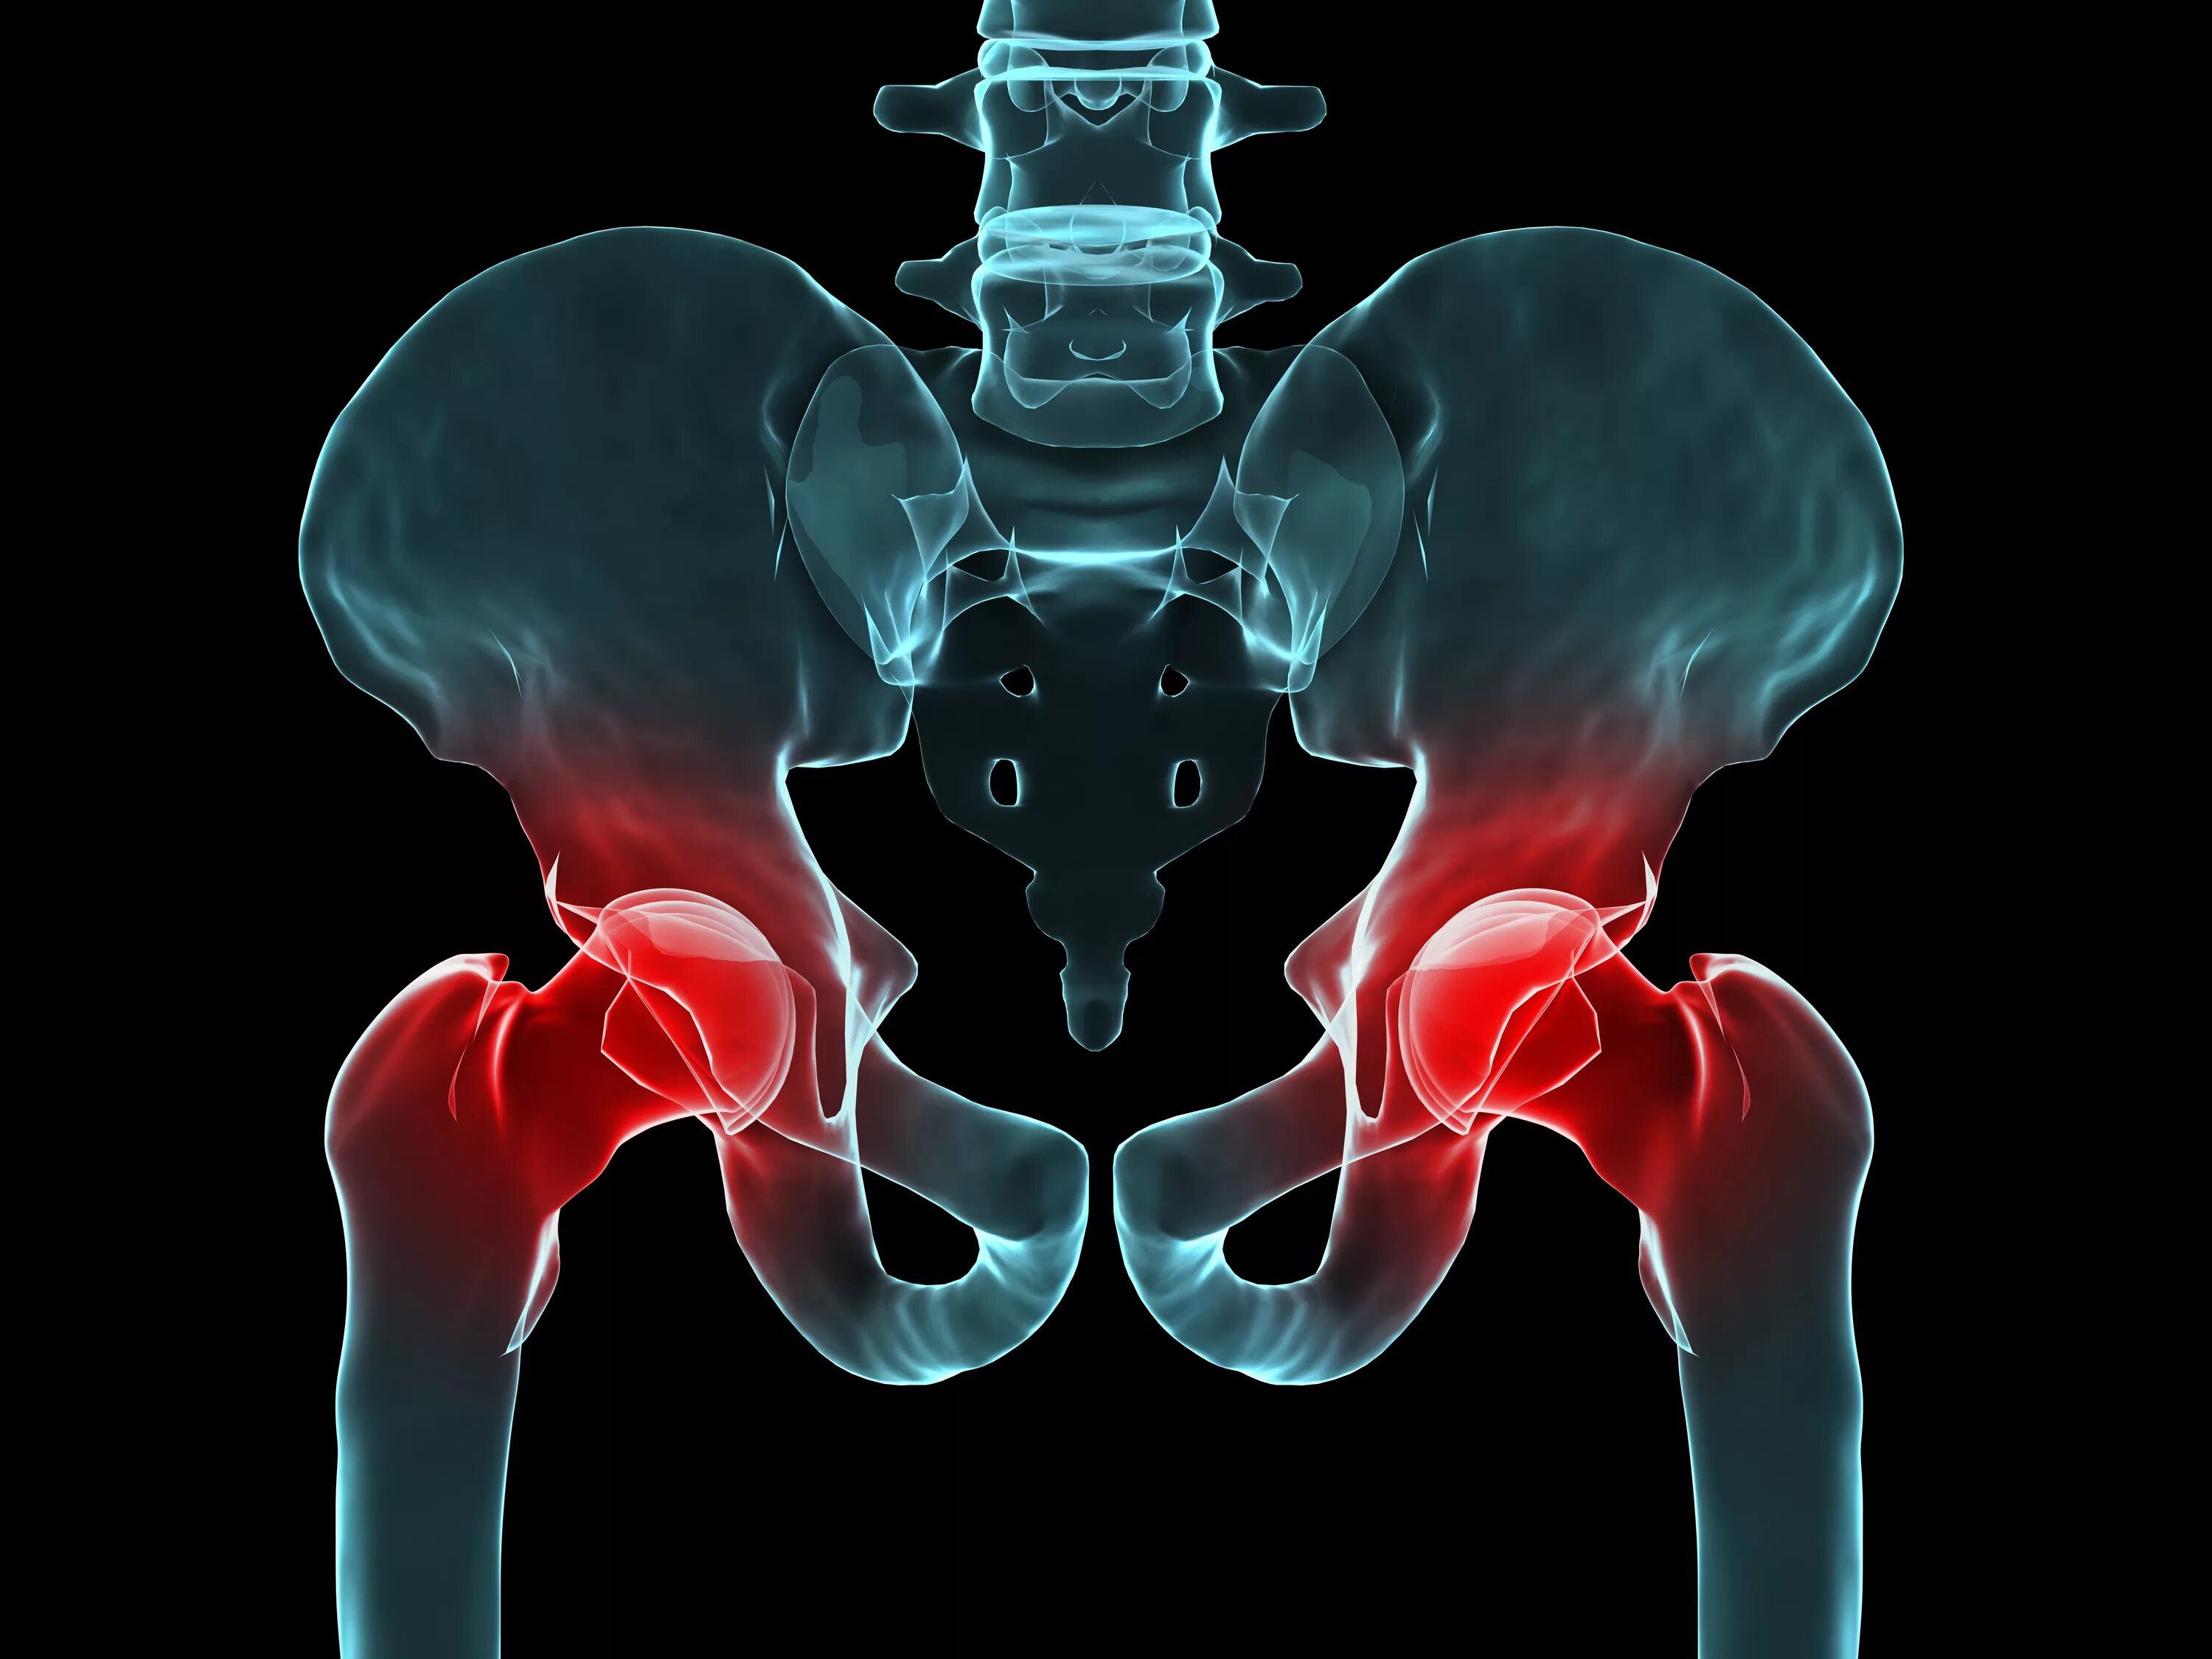

Тазобедренный сустав это